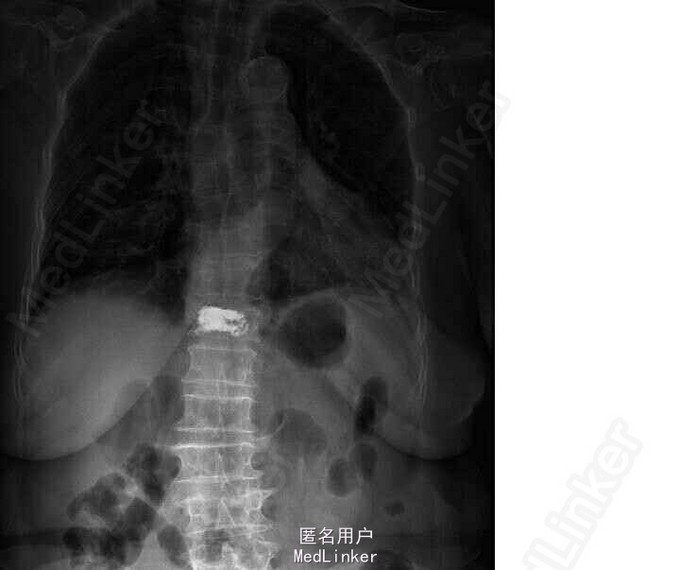

查体:胸腰段明显压痛及叩击痛。双髂嵴处压痛明显。 X线片示T11楔形变

诊断:胸椎压缩骨折(T11) 局麻下行椎体成形+活检术